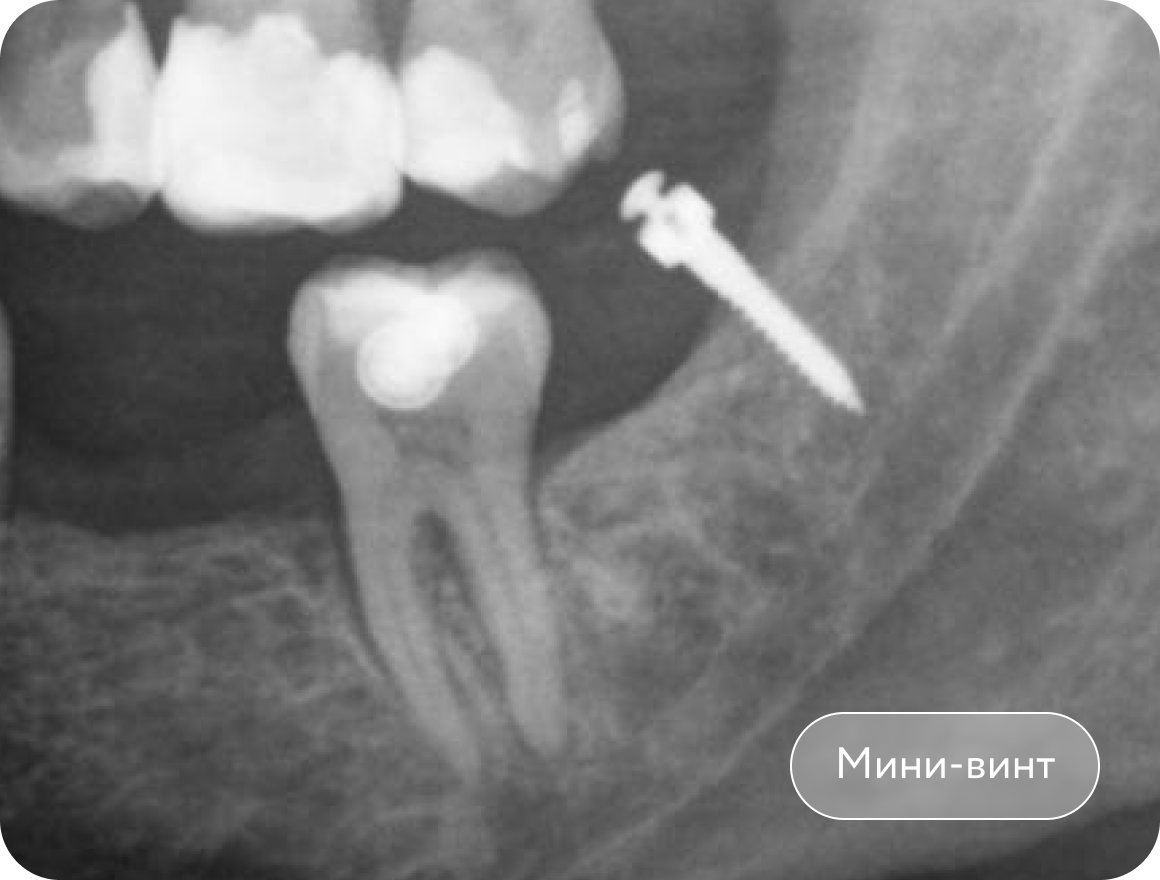

Установка мини-винта, вытягивание 2 моляра с помощью резинок. Создание места для имплантации в области 1 моляра. Срок лечения 3 месяца